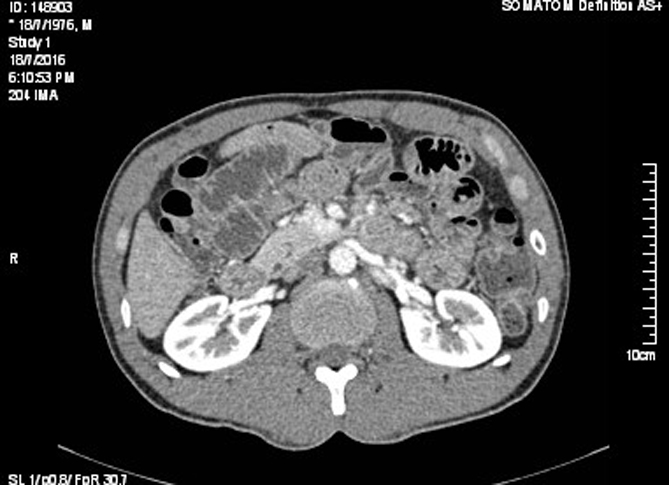

Image radiologique TDM normale de l'intestin :

Il y avait la difference de

image de intestin grele avec gros intestin ( colon )

en coupe TDM axiale . Intestin grele sont en pleine

du contenue , avec plusieure des plies muqueuse . La

colon avait moindre de plie muqueuse et sa diametre est grande et parfois presente

de poche a air . |

Images normales

de intestin grele en coupe sagitale .( Click

pour ouvrir agrandissement ) |